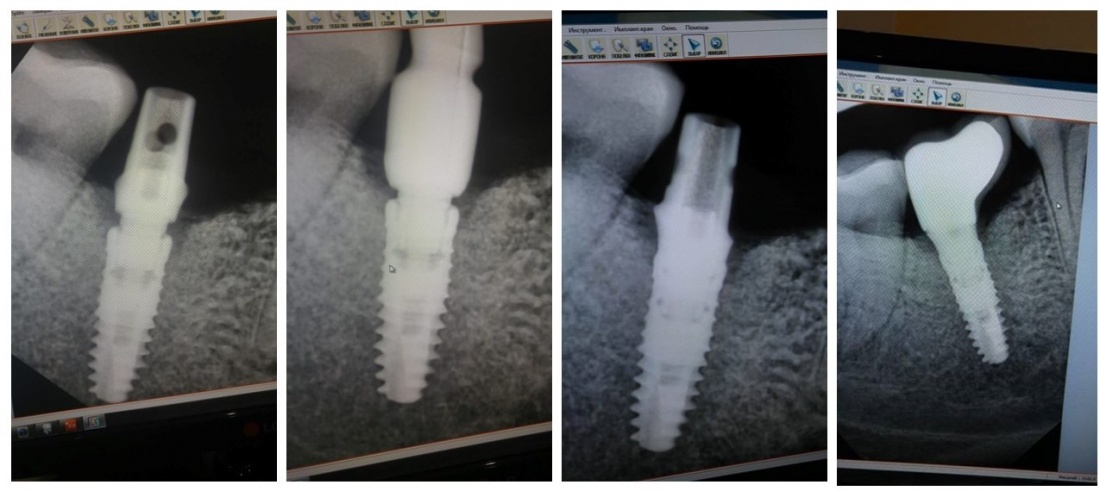

Мы сделали рентгеновские контрольные снимки —  панорамный для оценки положения имплантатов и прицельный для контроля посадки абатментов.

На последнем видно, что абатменты (особенно правого на фото зуба) не сели на свои места, между ними и платформами имплантатов есть щель — и эта ситуация наглядно демонстрирует, ПОЧЕМУ такие снимки необходимы. Мы вернули пациентку в хирургический кабинет и провели коррекцию абатмента (уменьшили ширину трансгингивальной части), После чего, проводили пациентку в кабинет стоматолога-ортопеда для временного протезирования.

После фиксации временных коронок мы делаем прицельный контрольный снимок для контроля посадки абатментов на платформу и оценки качества изготовления композитных реставраций.

Вот клиническая картина и рентгенологический контроль через 2,5 года после имплантации и протезирования:

Данные конусно-лучевой компьютерной томографии области имплантации через 2,5 года выглядят более интересными:

Как видите, под приемлемыми объёмами и состоянием десны в области имплантатов скрывается надёжный фундамент — восстановленная и сохраненная с помощью аугментации костная ткань, состояние которой за два с половиной года только улучшилось.